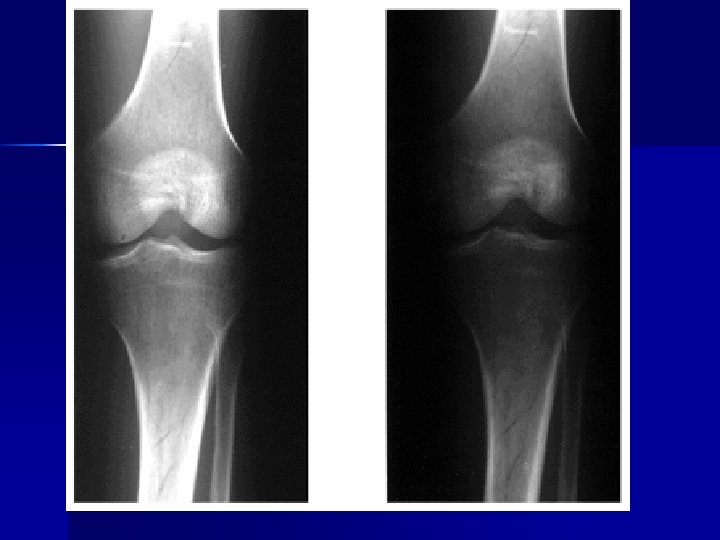

Evaluating Images What do you think?

n n n Does this show good detail? Is all of the anatomy present? How is the density / contrast?